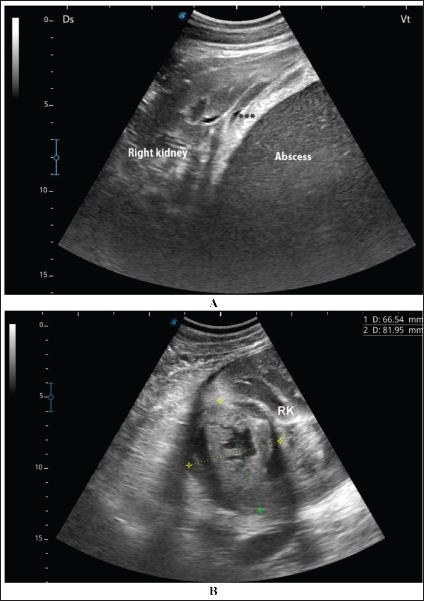

Fig. 7. Ultrasonographic findings in camel number 9 with abscessation of the right kidney-. The lesion appeared to compress the parenchyma of the right kidney (RK), its contents are hyperechoic, and its capsule is thick.

Fig. 8. Ultrasonographic findings in camel number 11 with right and left kidneys. Image A shows 2 abscesses within the right kidney (RK) and measuring 7.6 × 6.9 cm and 9.3 × 8.1 cm with isoechoic contents. Image B shows a relatively large abscess in the left kidney, and measuring 11.9 × 15.0 cm and with isoechoic contents.

Ultrasonographic findings in camel number 9 with right kidney abscesses are shown in Figure 7, where the lesion appeared compressing the parenchyma of the right kidney. Its contents are hyperechoic, and its capsule is thick. Figure 8 shows sonographic findings in camel number 11 with abscessation of the right and left kidneys. Abscesses measured 7.6 × 6.9 cm and 9.3 × 8.1 cm with isoechoic contents. A third abscess in the same camel was found within the left kidney. It was relatively large and was isoechoic. Ultrasonographic findings in camels 15 and 16 with abscesses of the left kidney are shown in Figure 9. A large abscess was found in camel number 15 with isoechoic contents and a thick capsule, while a small abscess was imaged in the left kidney of animal number 16 with heterogeneous contents. Figure 10 shows the ultrasonographic findings in camel number 17 with abscessation of the left kidney. A large abscess was found compressing the parenchyma of the left kidney with isoechoic contents. The urinary bladder in the same camel contained echogenic deposits that appeared to be highly echogenic.